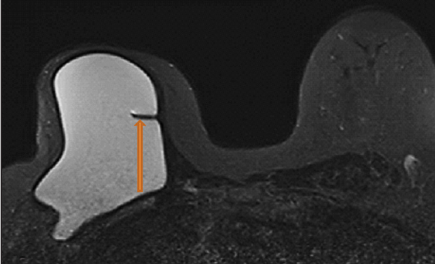

4. Chụp cộng hưởng từ tuyến vú trong đánh giá túi ngực

Cộng hưởng từ vú là phương tiện tốt nhất để xác định người bệnh có rách vỡ túi ngực hay không. Các chuỗi xung đặc biệt của cộng hưởng từ sẽ giúp đánh giá vỏ bao túi ngực, xác định tình trạng silicone trong và ngoài bao (nếu có).

Tuy nhiên, thuốc đối quang từ không cần thiết phải dùng khi chỉ cần đánh giá tính toàn vẹn của túi ngực. Chỉ nên sử dụng thuốc đối quang từ trong trường hợp cần đánh giá các đặc điểm của mô lân cận để xem xét tình trạng tân sinh.